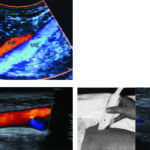

Luego de la visualización de las arterias se realiza, en simultáneo, el análisis espectral de velocidades. Se puede determinar rápidamente la normalidad o la presencia de estenosis a través de la trasformación en el examen del flujo homogéneo laminar y trifásico en un mosaico de colores con el incremento de las velocidades (Fig. 7, Fig. 8, Fig. 9 y Fig. 10). A nivel supra-patelar a cada arteria le corresponde una vena y a nivel infra-patelar, dos venas.

El estudio normal implica un flujo laminar, en sincronía con los latidos cardíacos, el examen de color homogéneo y un análisis espectral trifásico, con velocidades adecuadas de acuerdo al nivel arterial examinado (Fig. 13).

Incluye el examen de la pared del vaso, la caracterización de las placas, y el análisis del espectro en el segmento de la arteria previo a la lesión vascular, en el lugar de la lesión y en los segmentos posteriores (Fig. 14).

Las lesiones ateromatosas producen una pérdida de la deflexión prediastólica. En el lugar de la estenosis se produce un incremento de la velocidad sistólica, con ensanchamiento espectral y transformación del flujo laminar en turbulento (mosaico de colores). La fase diastólica puede incrementarse en base al grado de dilatación de las arterias periféricas y a la aparición de colaterales (Fig. 15).